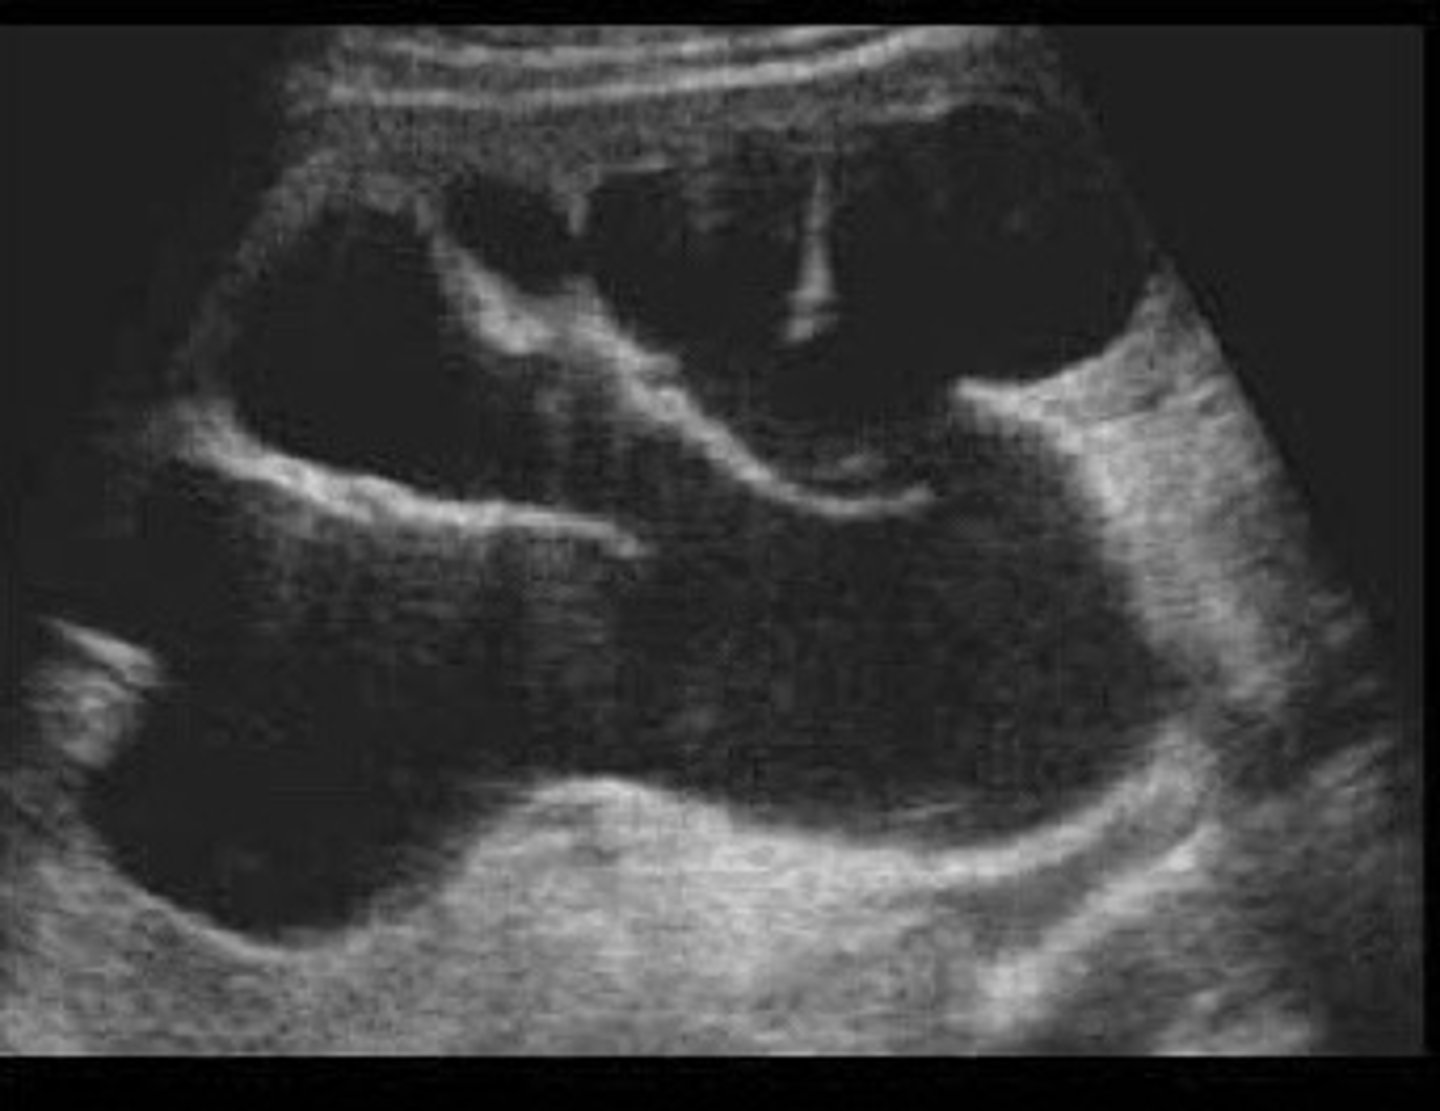

Nephrolithiasis

What does this image show

<p>What does this image show</p>